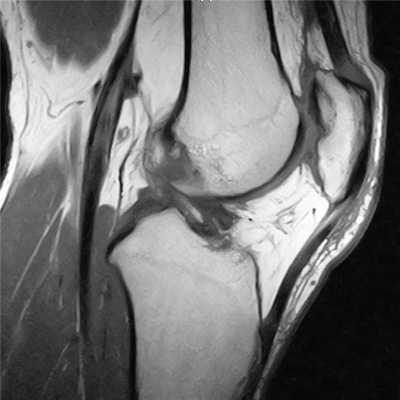

На снимке - разрыв крестообразной связки и мениска вследствие травмы колена

Для диагностики важна еще и форма мениска. В норме он в определенной плоскости имеет форму бабочки. Любые отклонения могут указывать на возможный разрыв.